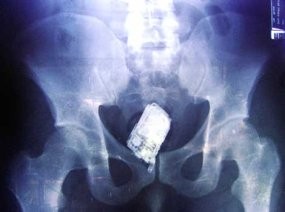

Pakistan - Ada-ada saja aksi para narapidana di Pakistan. Hanya karena ingin membawa ponsel ke sel tahanan, mereka nekat memasukkan alat komunikasi tersebut ke dalam tubuh.

Kejadian ini terjadi di kamp penjara berpengawasan ketat Gulzar Ahmad Butt, Pakistan, yang dilakukan oleh tujuh orang napi. Petugas penjara mengetahui hal ini ketika tengah melakukan pemeriksaan dengan metal detector.

Tak disangka dari pemeriksaan itu, seperti dikutip detikINET dari Cellular News, Senin (1/9/2008), ditemukan sebanyak 30 ponsel dari ketujuh napi ini. Ponsel-ponsel tersebut tersembunyi di rektum para napi.

Rektum adalah ujung dari usus besar yang letaknya berada dekat anus. Petugas pun langsung melakukan tindakan medis untuk mengeluarkan ponsel-ponsel tersebut.